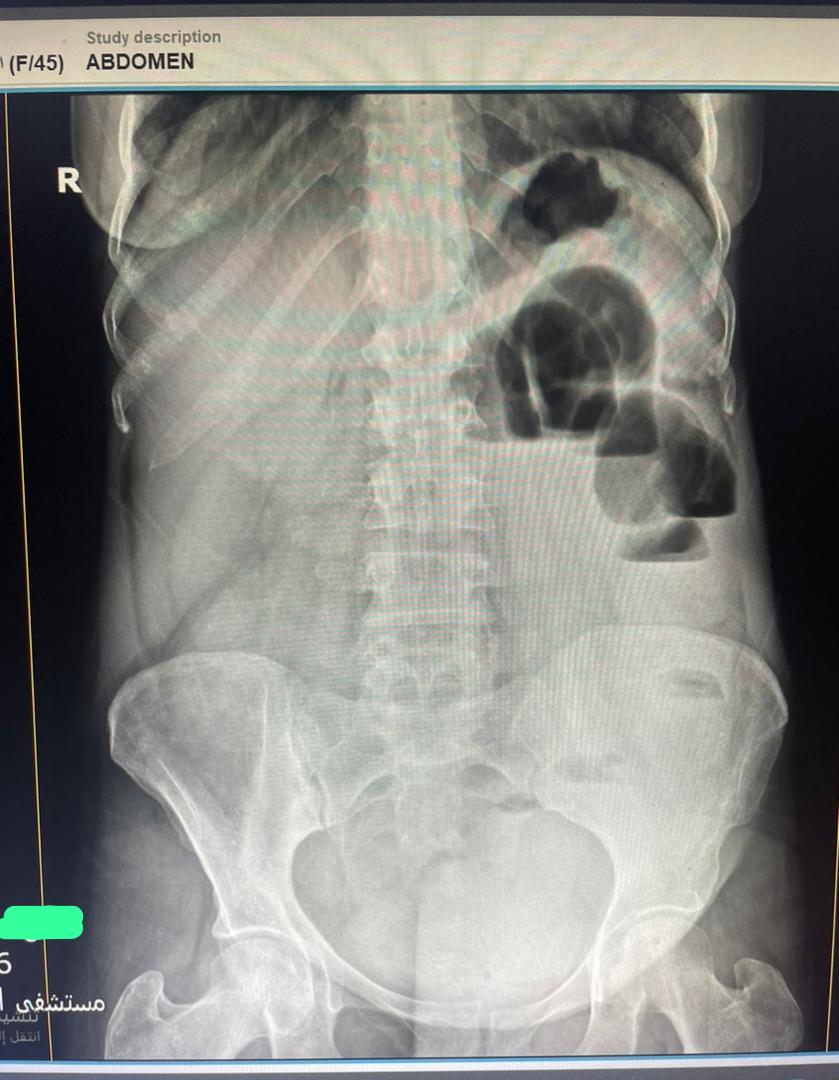

45 years female Presented with diffuse abdominal pain , persistent vomiting and bloody stool And a palpable abdominal mass seen to the RT of the umbilicus #EchoTech #Ultrasound #GIT

45 years female Presented with diffuse abdominal pain , persistent vomiting and bloody stool And a palpable abdominal mass seen to the RT of the umbilicus #EchoTech #Ultrasound #GIT

45 years female Presented with diffuse abdominal pain , persistent vomiting and bloody stool And a palpable abdominal mass seen to the RT of the umbilicus #EchoTech #Ultrasound #GIT